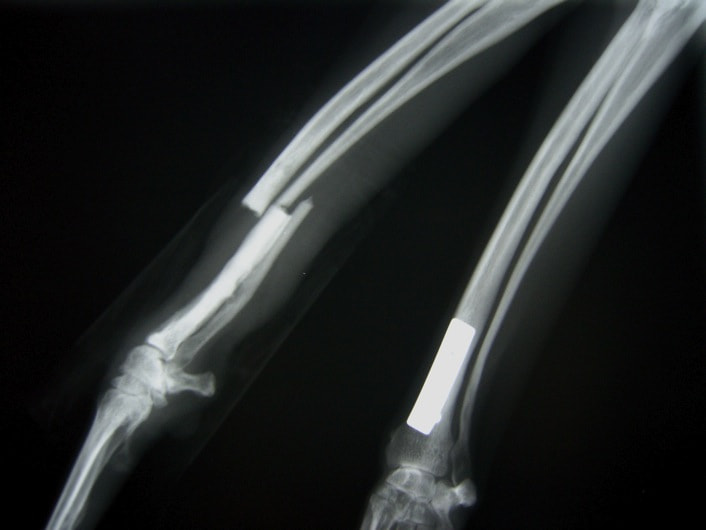

症例3:キルシュナーワイヤーのピンニングによる整復

ペルシャ猫 11ヶ月齢 雄

他院にて左大腿骨遠位の成長板骨折(salter-harrisⅠ型)が認められており、治療相談を目的として来院。当院にて、キルシュナーワイヤーを用いたピンニングにより骨折部位の整復を行いました。術後の経過は良好で、現在も経過観察中です。

術前レントゲン

術後レントゲン